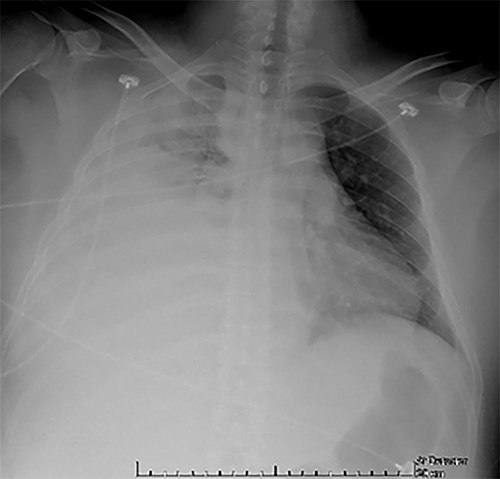

Examination revealed tachycardia, tachypnea, jaundice, dehydration, jugular vein distension, right lung hypoventilation, ascites, upper abdominal tenderness and bilateral lower limb edema. Laboratory workup highlighted neutrophilic leukocytosis, with WBCs exceeding 20 000/μl, along with an abnormal hepatic function panel. The latter showed hypertransaminasemia with ALT predominance over AST (344.7 U/L and 288.5 U/L, respectively), hyperbilirubinemia (10.01 μmol/L) and elevated values of ALP (909.1 U/L) and DHL (709.9 U/L). Of relevance, creatinine elevation (2.11 mg/dl), thrombocytosis (629 × 109/L) and positive D-Dimer (5780 ng/ml) were also noted, so acute kidney injury management and thromboprophylactic measures were initiated. A chest X-ray (CXR) showed a massive right pleural effusion (Fig. 1) and an abdominal ultrasound (US) revealed hepatomegaly with a right nodule (Fig. 2). After further evaluation, tomographic evidence of a right pleural effusion occupying 100% of the lung (Fig. 3) and a 20 cm hypodense, nodular lesion in the right liver (Fig. 4) were identified. These findings were suggestive of an ALA concomitant with an empyema. The patient was admitted into the intensive care unit and prepared for surgery.

CXR at admission: right pleural effusion occupying 90% of the lung.